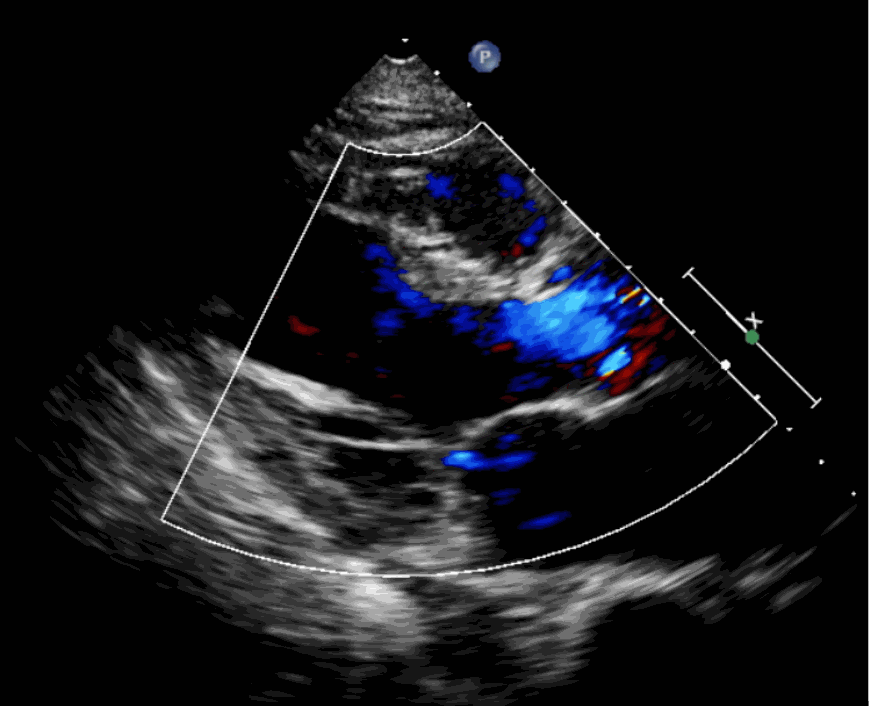

該例患者為62歲,女性,因“間歇性心悸、胸悶、氣短、胸痛1年,加重1周”之主訴入院。入院診斷:主動脈瓣重度關(guān)閉不全,二尖瓣、三尖瓣輕度關(guān)閉不全,心功能III級;冠狀動脈粥樣硬化性心臟病。行心臟超聲心動圖提示“主動脈瓣重度關(guān)閉不全;瓣口水平以下左室下壁、后下壁搏幅減低;EF值 0.30,左房、左室大、右房大小正常高限;二尖瓣、三尖瓣關(guān)閉不全;輕度肺動脈高壓(收縮壓42mmHg);主動脈硬化;左室收縮功能重度減低。經(jīng)心血管外科劉洋、楊劍教授、麻醉科陳敏教授及超聲科孟欣教授等專家團(tuán)隊(duì)綜合評估,判定患者為外科手術(shù)高?;颊?。

術(shù)前超聲影像圖